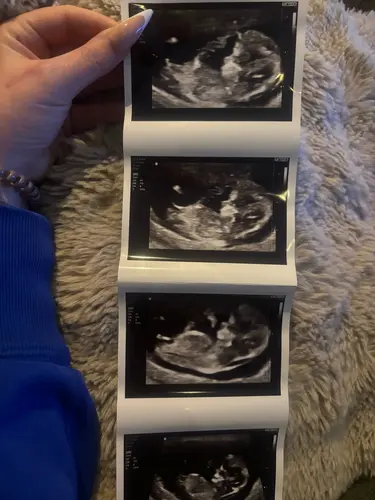

Mijn termijn echo 1-8-26